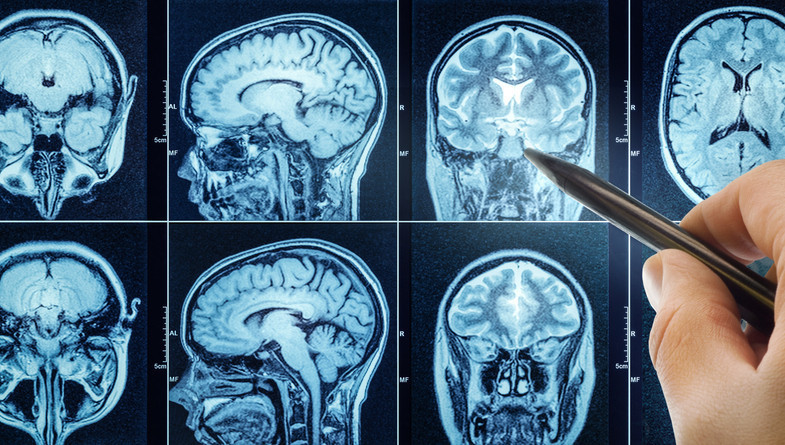

Modern teknolojiler ameliyat başarısını artırıyor

Beyin cerrahisinde artık "daha çok kesi" değil, "daha akıllı cerrahi" ön planda oluyor. Hibrit ameliyathanelerde kullanılan ileri teknolojiler sayesinde operasyonlar çok daha güvenli hale geldi.

Bu kapsamda nöronavigasyon teknolojisi cerraha tümöre ulaşması için en kısa ve güvenli rotayı belirleyen dijital bir yol haritası sunarken; fonksiyonel MR ve traktografi yöntemleri beynin konuşma, hareket ve görme gibi hayati merkezlerini haritalandırarak bu kritik bölgelerin korunmasına yardımcı oluyor.